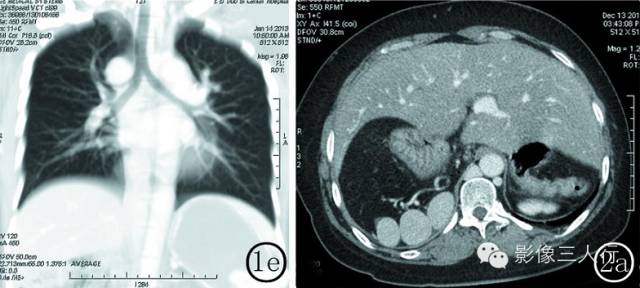

图 1 女性 , 32 岁 。 图 1a 肝段下腔静脉缺如 ,奇静脉异常扩张 。 图 1b 脾位于胃体后方 ,呈一类圆形团块影 ,胰腺体尾部缺如 ,胃旋转不良 。图 1c 双侧肾静脉回流入奇静脉 ,小肠均位于腹腔右侧 ,结肠位于腹腔左侧 。 图 1d 腹腔干及肠系膜上动脉共干 ,起始部明显狭窄 ,腹腔干发

育细小 ,仅发出一支脾动脉 ,肠系膜上动脉向上发出肝总动脉及胃左动脉 。 图 1e 右肺上叶支气管发育细小 ,右肺上叶容积减小